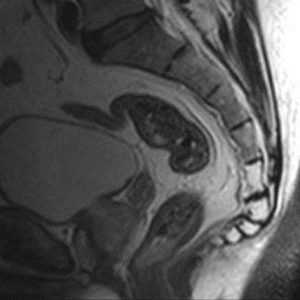

Рентгеновские снимки крестцово-копчикового отдела позвоночника